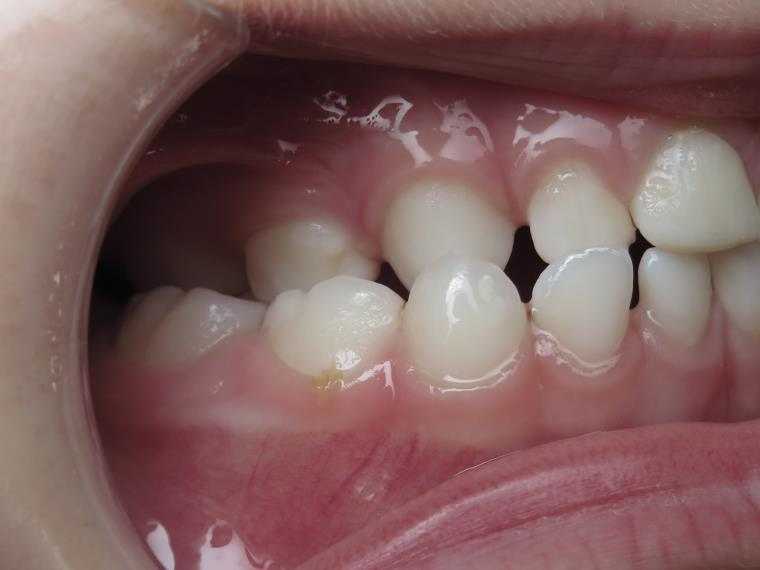

7.inversé droit 4 ans

inversion des dents postérieur coté droit

bilan début et en cours de traitement